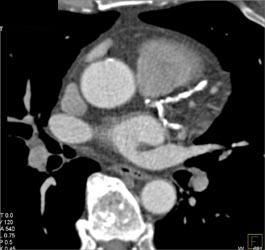

Calcified Plaque in LAD